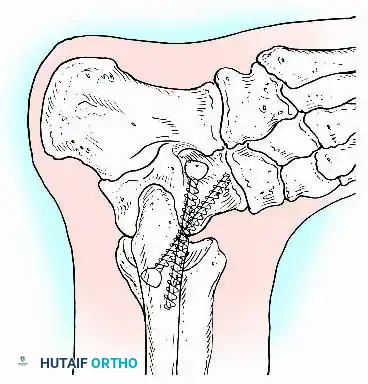

Internal fixation is currently the preferred method for uncomplicated ankle arthrodesis due to higher union rates, superior patient comfort, and the elimination of pin-tract infections. Biomechanical studies demonstrate that crossed, large-diameter (6.5 mm or 7.3 mm) cannulated cancellous screws provide exceptional resistance to shear and torsional forces.

A standard construct involves two or three screws:

1. A "home run" screw directed from the posterior malleolus into the anterior neck of the talus.

2. A screw from the medial malleolus into the lateral body of the talus.

3. A screw from the anterolateral tibia into the medial talar body.